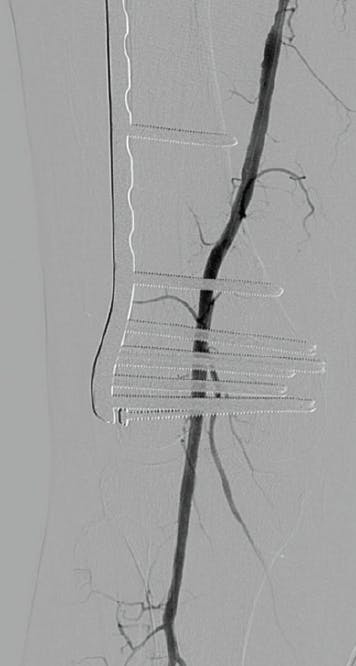

Arteriographically, the inflow (iliac, common femoral artery, profunda femoral artery) was patent. Her superficial femoral artery (SFA) was occluded with an isolated segment of patent popliteal artery with no identifiable tibial artery below the knee (Figure 1).

Figure 1. Arteriogram showing ostial right SFA/popliteal artery occlusion.